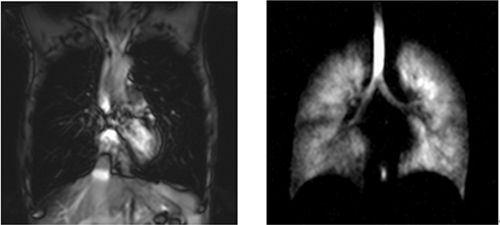

传统的人体质子肺部磁共振图像(左)及经过点亮之后的我国首幅人体超极化气体肺部磁共振影像(右)武汉物数所9月7日获得中国首例肺部病人的气体磁共振影像。

在基金委国家重大科研仪器设备研制专项“用于肺部重大疾病研究的磁共振成像系统研制”的资助下,在基金委医学部和中科院的大力支持下,科研人员使用级联激光光泵的核心技术,成功研制出了气体产率高、控制自动化、可移动式的129Xe气体极化装置,能够将原子核自旋的极化度增强倍数提高到44000倍以上。他们所研制新型的人体“马夹式”高灵敏肺部成像探头,提高了肺部气体磁共振信号的激发均匀性和接收效率。他们提出的化学位移交换翻转转移(CEIT)等序列,能够高效并定量获得肺部O2-CO2交换、O2-血液交换的动力学和影像学信息。目前,该团队已经获得了我国首幅活体超极化129Xe动物及人体磁共振影像。同时团队还利用该项技术对肺部的气血交换时间、气血交换膜厚度、肺泡表面体积比等参数进行了定量研究,并成功区分了健康及疾病模型。该项目的这些研究成果已经在磁共振医学的国际专业杂志上发表,并获得了国际同行专家的认可。近日,该研究小组已经开始了这项技术的临床前研究,通过与武汉大学中南医院吴光耀团队合作,获得了我国首例肺部病人(哮喘)的气体磁共振影像,相比传统CT检查,该技术能无侵入、无放射性地可视化肺部通气缺陷,从而为早期肺部疾病提供了全新的影像学技术。

超极化129Xe肺部磁共振成像技术突破了传统磁共振不能对肺部成像的限制,成功“点亮肺部”,该技术使用的超极化惰性气体129Xe安全无毒,良好的脂溶性和化学位移敏感性,使其在肺部气血交换功能探测上具有独特的优势,是对现有的肺部成像技术的有效补充,在肺部疾病早期检测方面具有极大的潜力。